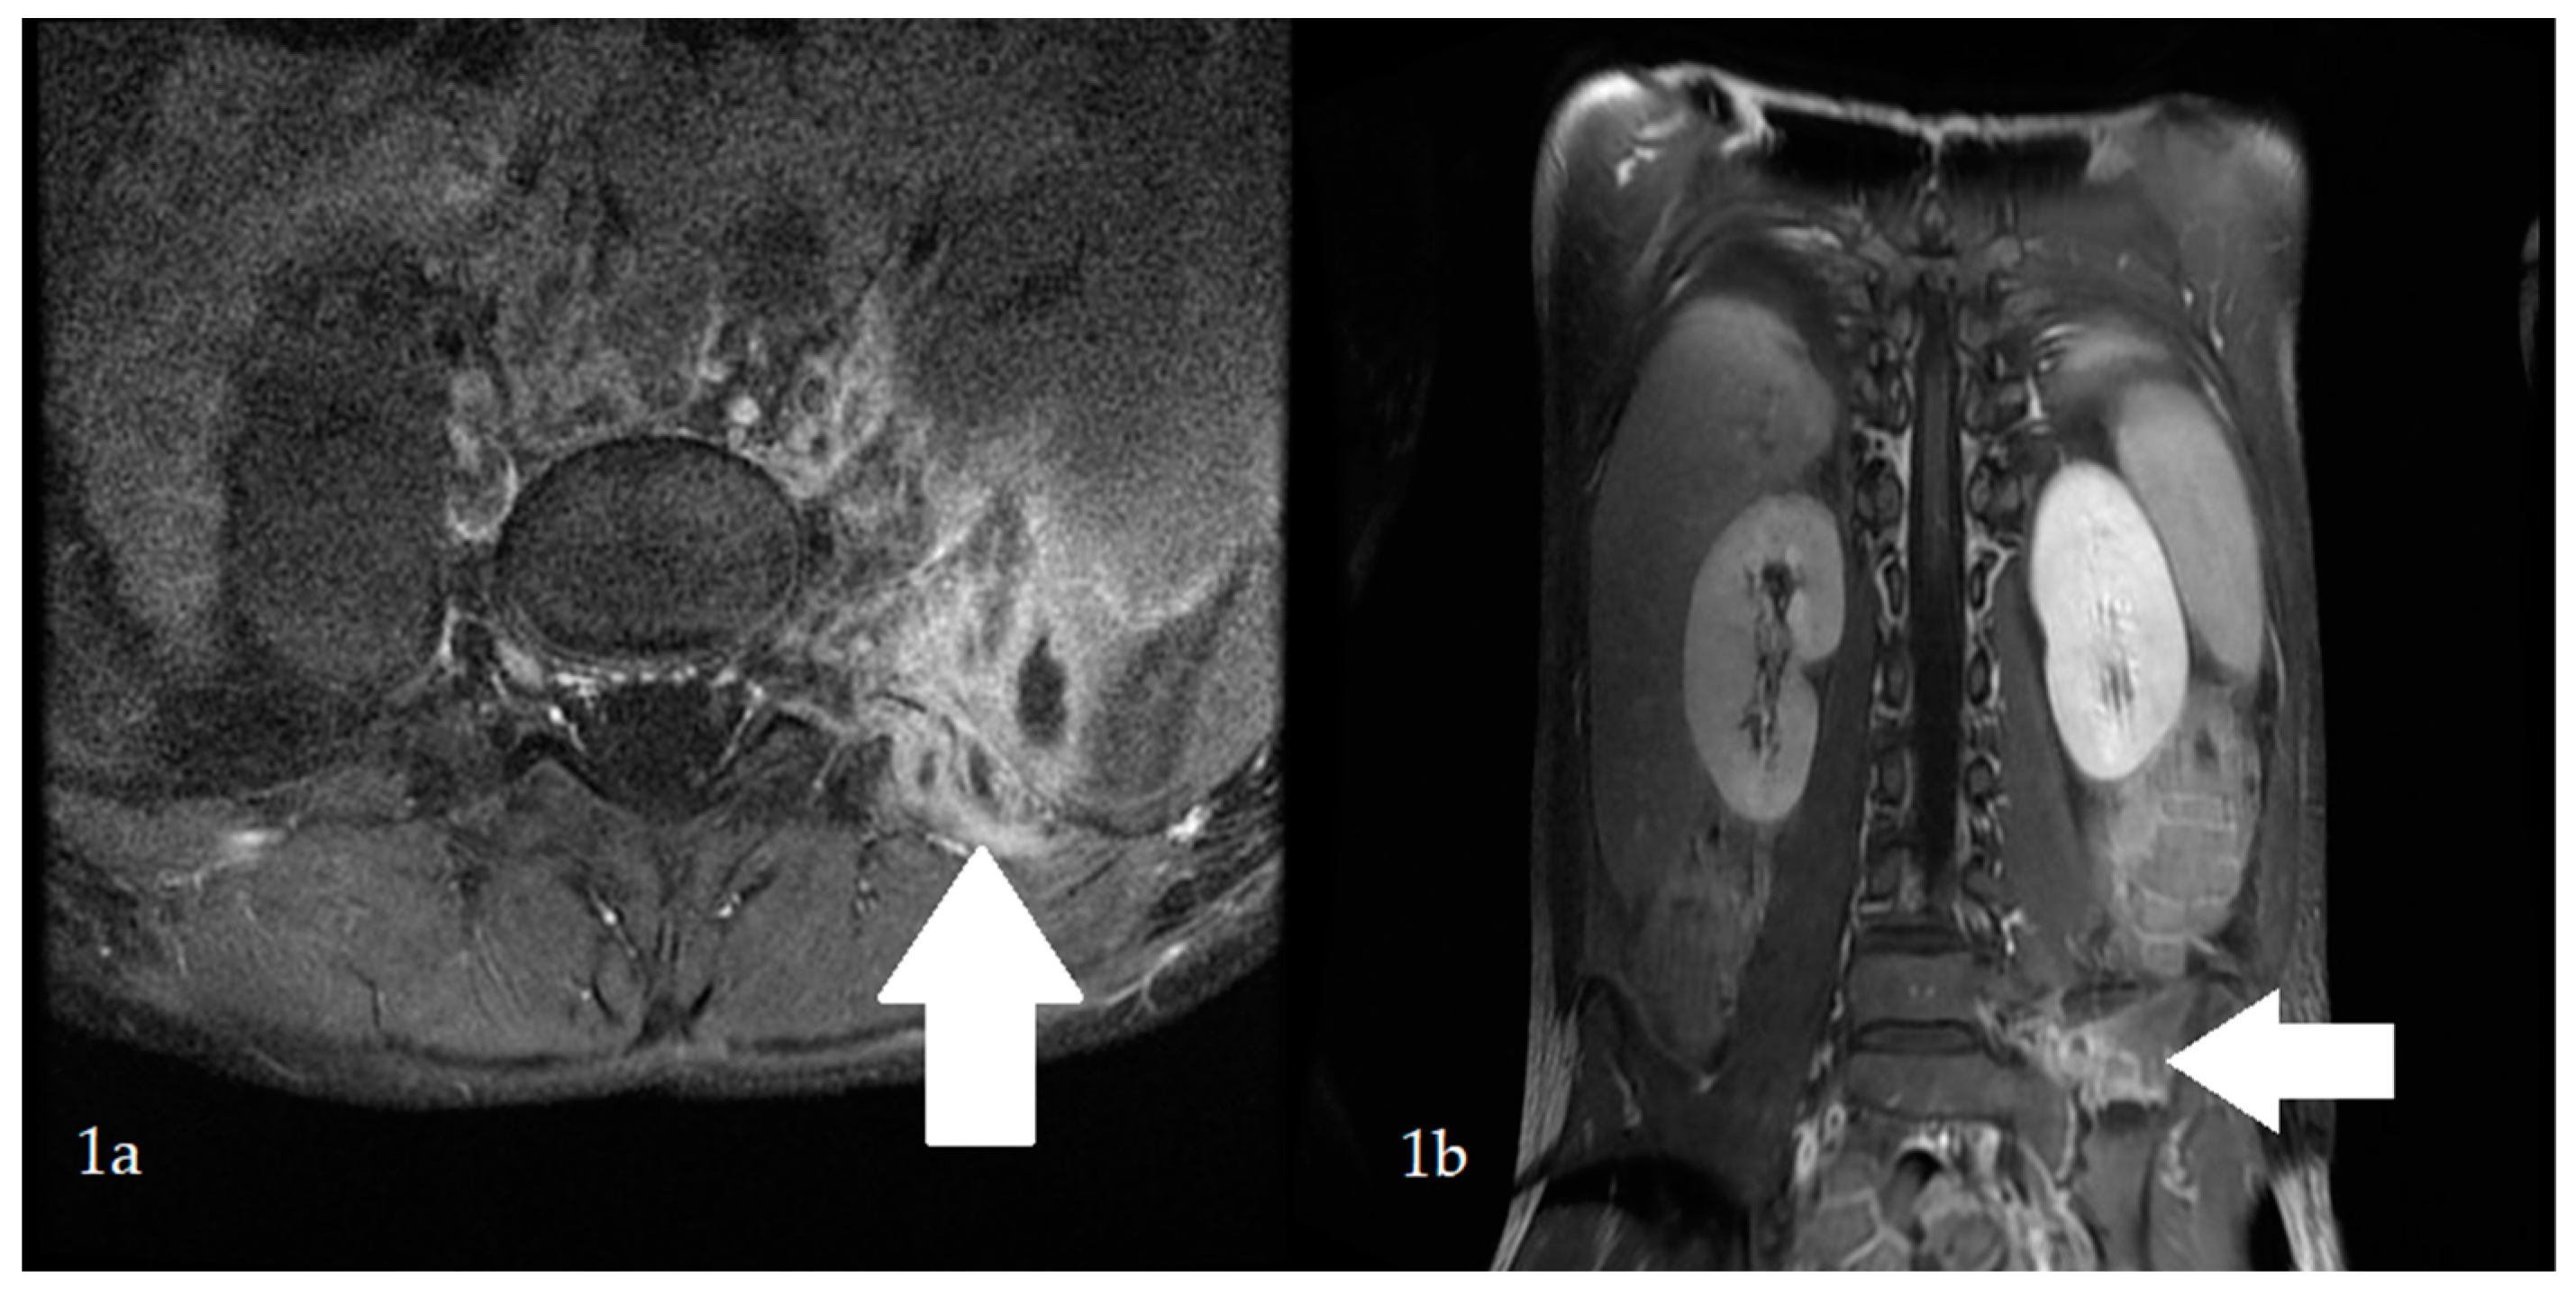

On day 3 after surgery, physical examination revealed a loud systolic murmur above the heart. Based on the clinical course and preliminary echocardiography, infective endocarditis (IE) was suspected. Transthoracic echocardiography revealed an abscess and mitral valve regurgitation (Figure 2). Laboratory tests showed an elevated concentration of NT-pro BNP (519 pg/mL). Spironolactone was administered, and antibiotic therapy was continued for a total of 40 days. The boy’s general condition improved, and normalization of laboratory parameters was achieved. After four weeks of treatment, the abscess was no longer visible, as confirmed by transesophageal echocardiography.

Figure 2. Echocardiographic examination: a hypoechoic spherical space of (cross-shaped markers) 9–10 mm in diameter can be seen at the root of the posterior leaflet of the mitral valve, which may correspond with an abscess. Moderate mitral regurgitation 8–9 mm can also be observed, reaching the apex of the left atrium.